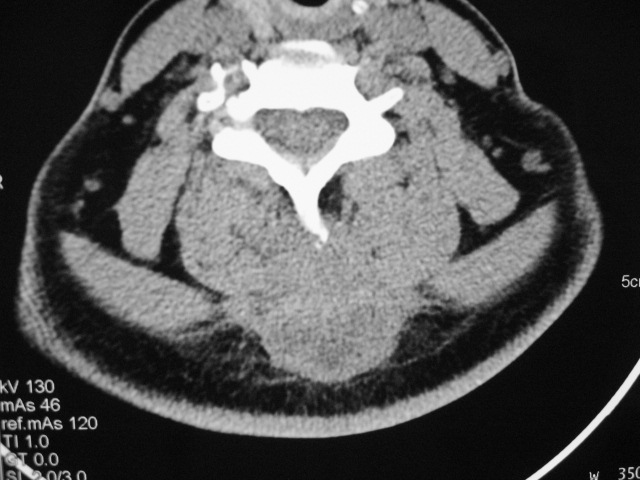

女,46岁,发现颈后区肿块3月余.

颈后软组织肿块,内可见坏死区及点状钙化,邻近颈椎棘突可见破坏,邻近肌间隙模糊,肿块周围脂肪间隙可见索条状影。

考虑:1)感染,结核可能;

2)肿瘤不能排除。